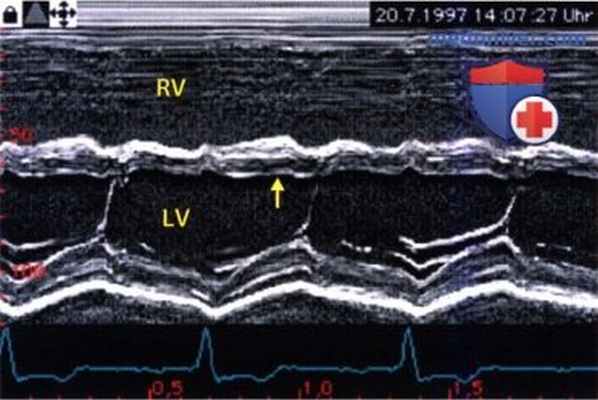

Эхокардиография в М-режиме, выполненная из парастернального положения датчика при нагрузке объемом на правый желудочек.

Выявлено типичное увеличение правого желудочка (RVDd/LVDd=1) и снижение амплитуды движений межжелудочковой перегородки (стрелка).